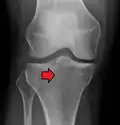

Lipohemarthrosis (presence of fat and blood from bone marrow in the joint space after an intraarticular fracture) seen on X-ray in a person with a subtle tibial plateau fracture -

Subtle tibial plateau fracture on an AP X ray of the knee -